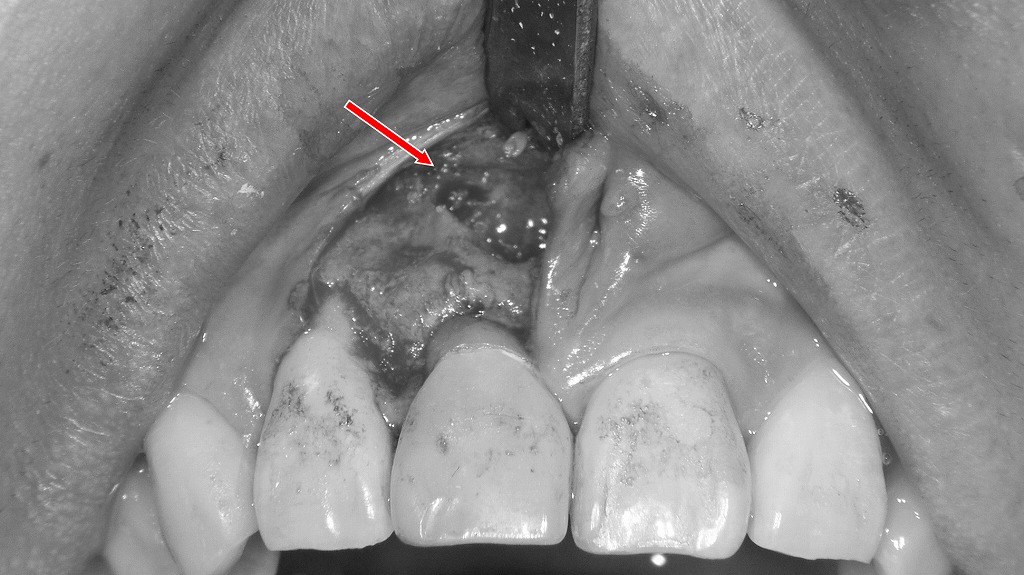

前歯部の根尖病巣を除去する歯根端切除術の実際

この画像は、上顎前歯部の歯根端切除術(apicoectomy)を行っている術中の所見を示しています。

赤い矢印の位置に、歯根の先端部(根尖)と周囲の病変を露出している状態です。

✔ 術野の状態

- 粘膜を剥離し、歯槽骨を開削して根尖部に到達したところです。

- 露出している部分には、肉芽組織や感染組織が付着しており、これを除去することで病巣を取り除く治療を行います。

- 歯根の先端は感染により変色・不整形になっていることが多く、必要な長さを切除して健全な歯根面を確保します。

✔ 歯根端切除術の目的

- 根管治療だけでは改善しない**根尖性歯周炎(根の先の膿)**を外科的に除去する手術。

- 感染した根尖部と病巣を直接目視下で切除・清掃し、再発を防ぐことが目的です。

✔ 術式の流れ(画像の段階)

- 粘膜切開→剥離して骨面を露出

- 歯槽骨の開削

- 根尖と炎症性組織の露出 ← 画像はこの段階

- 根尖切除

- 病巣掻爬

- 必要に応じて逆根管充填

- 創部を縫合